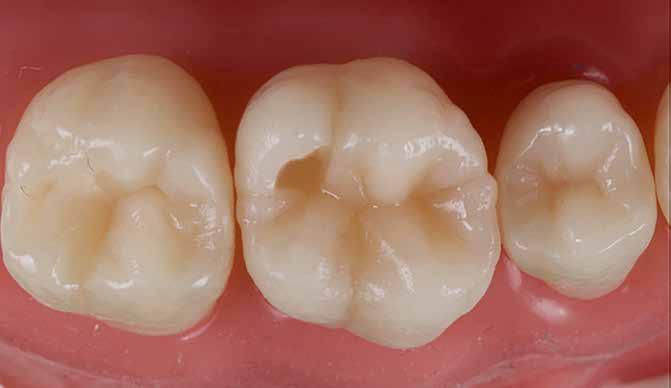

A restauráció polírozását korongok és szilikonpolírozók kombinációjával végezte, majd az okklúzió ellenőrzését követően a pácienst a rendelőből otthonába bocsátották. Megjegyzendő, hogy a finírozást követően az eredeti okkluzális anatómia csak minimális mértékben módosult (17. ábra).

2. eset

Egy 26 éves páciens a jobb felső első molárisának ideiglenes, endodonciai kezelést követő, I. osztályú restaurációjával jelentkezett. Mivel a fogban jelentős mennyiségű dentin és zománc volt jelen, valamint a marginális peremek épek voltak, a páciens tájékoztatása és beleegyezése után a kezelési terv a direkt kompozit restauráció volt (18. ábra). A fog preparálása az 1. esetben leírtak szerint történt (19. ábra).

Végül a szerző az üreget a „Modified Super-Closed Sandwich Approach” [20] technikával állította helyre (amely a klasszikus rezin-módosított üvegionomer zárt-szendvics technika módosított változata), és az okkluzális iránytű módszerét alkalmazta a rágófelszín lezárására (20. ábra).